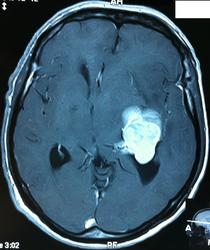

Начало вот здесь http://www.radiomed.ru/cases/kt-gms-obemnoe-obrazovanie-levoi-gemisfery-bolshogo-mozga-vnutrizheludochkovaya-meningioma. Пациент оперирован (меня сначала дезинформировали по поводу операции), перед операцией состояние ухудшилось, возникла правосторонняя гемиплегия, которая осталась и после декомпрессии. МРТ, КТ снимки и выписку предоставила супруга пациента, снимал на iphone, простите за качество, дисков с исследованиями не записывали. Надеюсь вопрос по данному случаю исчерпан.

Вот "цветочки":

T1+C

Т2

FLAIR

И Вы считаете, что эта опухоль имеет интравентрикулярную локализацию?

Изначально по КТ я так предпологал, а теперь на 100% уверен, разве МРТ это не показало? Гистологически - менингиома, опухоль мозговой оболочки. Покажите, пожалуйста, образование где-нибудь прилежит к костям, где есть мозговая оболочка? Я не вижу, зато отчетливо вижу в левом боковом желудочке из оболочек сосудистого сплетения. Что вас еще смущает? По-моему, предостаточно фактов, чтобы развеять все сомнения.

Мне видится так. Иначе в данной локализации просто неоткуда расти оболочечной опухоли. На контрольной КТ, после декомпрессии, когда срединные структуры стали действительно срединны, правое обызвествленное сосудистое сплетение видно отчетливо, а левое, где оно? Ведь если бы образование компремировало, то после операции, когда часть мозга пролабировало в трепанационное отверстие мы бы увидели и левое сосудистое сплетение, но оно интимно связано с образованием и даже "потянулось" за ним в сторону декомпрессионного отверстия, потому что это и есть "росток" откуда выросла опухоль.